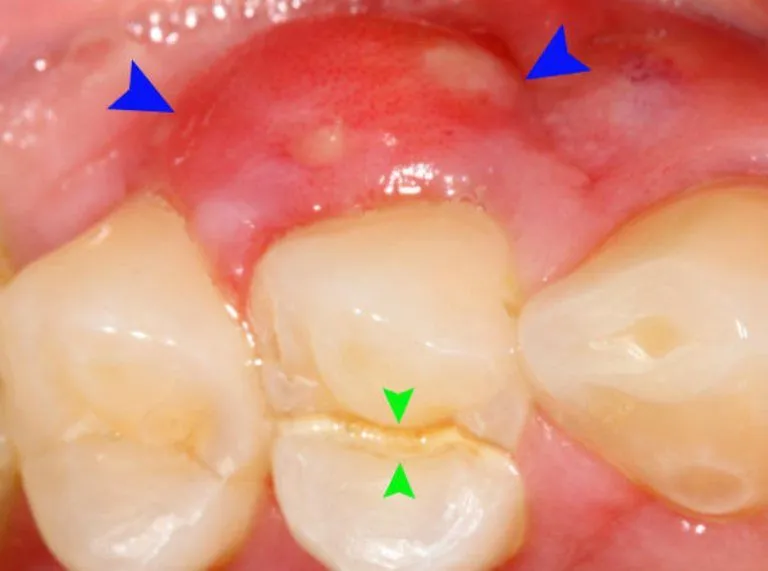

Tình trạng bị sưng lợi chân răng không còn xa lạ với nhiều người, từ trẻ em đến người lớn. Mặc dù đôi khi chỉ là một

Nướu sưng (hay còn gọi là sưng lợi) là một tình trạng răng miệng khá phổ biến, gây ra không ít phiền toái và đau nhức cho